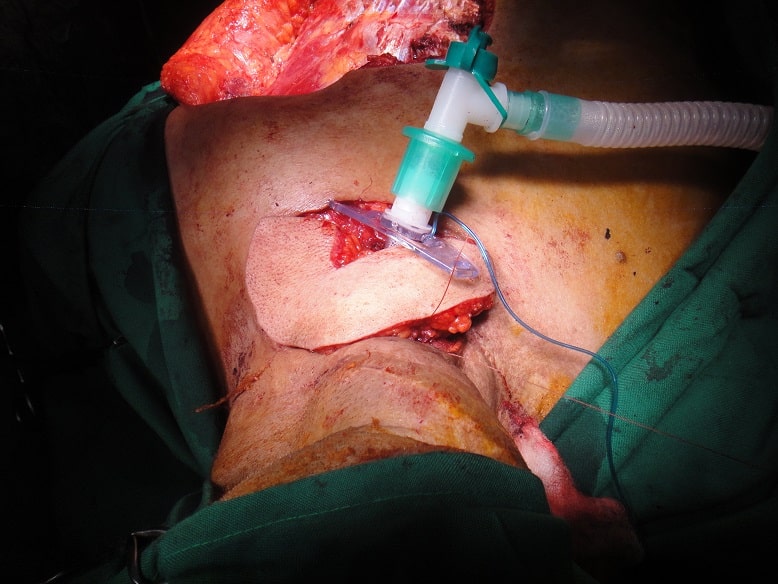

32 YEARS OLD MALE SUFFERING FROM RIGHT LOWER GINGIVO BUCCAL MUCOSA CARCINOMA INVOLVING RIGHT RETROMOLAR TRIGONE.PATIENT HAS ACTIVE PULMONARY TUBERCULOSIS.RIGHT RADICAL NECK DISSECTION WITH RIGHT DISTAL MANDIBULECTOMY WITH RIGHT LOWER ALVEOLECTOMY WITH RIGHT PECTORALIS MAJOR MYOCUTANEOUS FLAPE DONE.

31-12-2021